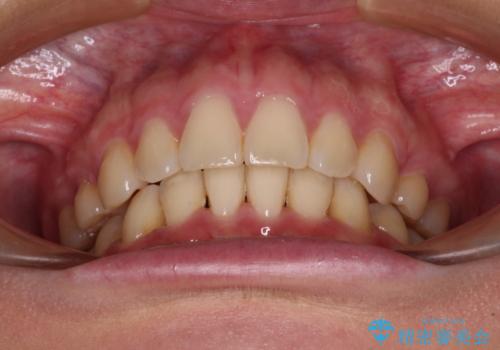

上顎前突 目立たないワイヤー装置での抜歯矯正

- 口元の突出感改善を希望して来院された患者様です。

口元を積極的に引っ込めるために、上下左右の小臼歯計4本を抜歯することとしました。

咬み合わせが深いため、咬み合わせの高さを向上させながら口元を下げることとしました。

左右ともに下顎に対して上顎歯列が前方位にある上顎前突であったので、上顎歯列全体を後方に移動させることで上下咬み合わせを改善し、その上で抜歯矯正により口元の突出感を改善させていきました。